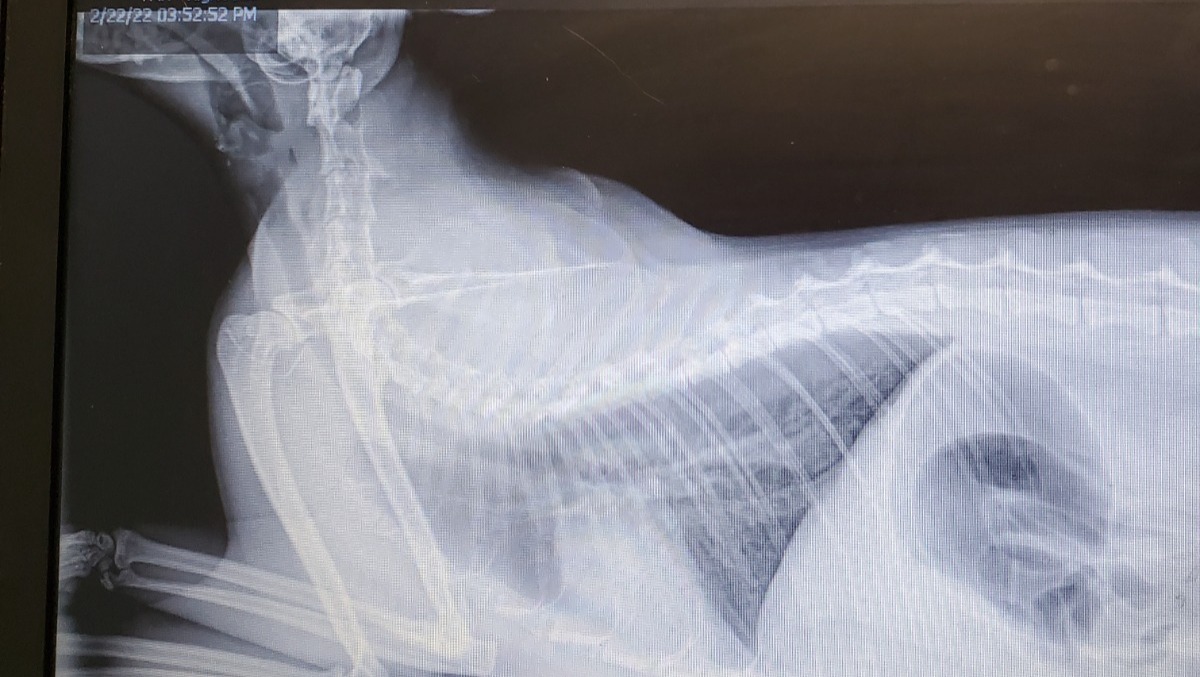

Hi there. My name is Hallie and I am raising funds for my little cat Rani. Rani is 6 years old and the sweetest cat I've ever had the pleasure of knowing. Recently, she has developed some breathing problems. I took her to the vet who immediately referred her to NCSU's vet hospital and quoted me at between $2000-$5000 for a procedure to remove a mass that was blocking almost her entire trachea and esophagus. The vet has asked for $2000 up front as a deposit as they claimed that was on the low end of what it will end up costing. I am looking for assistance in paying this bill. After chatting with my pet insurance provider it does not appear it is covered due to the fact that we are still in the waiting period for coverage and that it may have been a pre-existing condition prior to signing her up. So, paying this bill in its entirety comes down to me. I work in the service industry, as such my income is variable. I really want to take care of my baby, but also not ruin myself financially doing so.